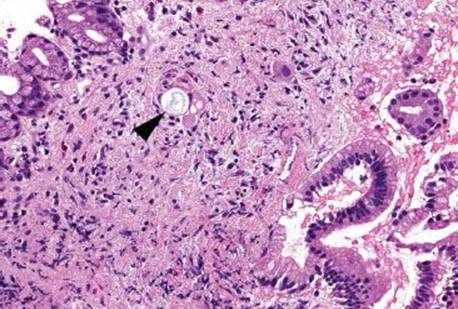

This case was received as “prominent ampulla, concerning for malignancy” (Fig. 3.313). The initial sections show duodenal mucosa with acute and chronic inflammation, gastric foveolar metaplasia, and marked reactive epithelial change (Fig. 3.313). Although these histologic features can account for a nodular clinical impression, deeper sections were pursued based on the clinical suspicion for malignancy. The first set of deeper sections were similarly concerning, but definitive malignancy was not seen. Deeper sections were repeated. And repeated. And repeated. In this case, the tissue block was exhausted and on the 38th level (!!!), clear lymphovascular invasion and infiltrating adenocarcinoma were seen (Figs. 3.314 and 3.315). When the histology does not fit the clinical scenario, consider deeper sections. When the deeper sections are not conclusive, consider repeat deeper sections or recommend rebiopsy (in this case, the patient was too unstable for a subsequent biopsy).

Figure 3.314 Infiltrating poorly-differentiated adenocarcinoma and lymphovascular space invasion. Deeper sections were performed until the block was exhausted. This photomicrograph represents the 38th (and final) section, which shows desmoplasia, infiltrating adenocarcinoma (arrowheads), and lymphovascular space invasion (asterisk). These deeper sections show an entirely different biopsy compared to the initial sections and were sufficient for chemotherapy initiation.